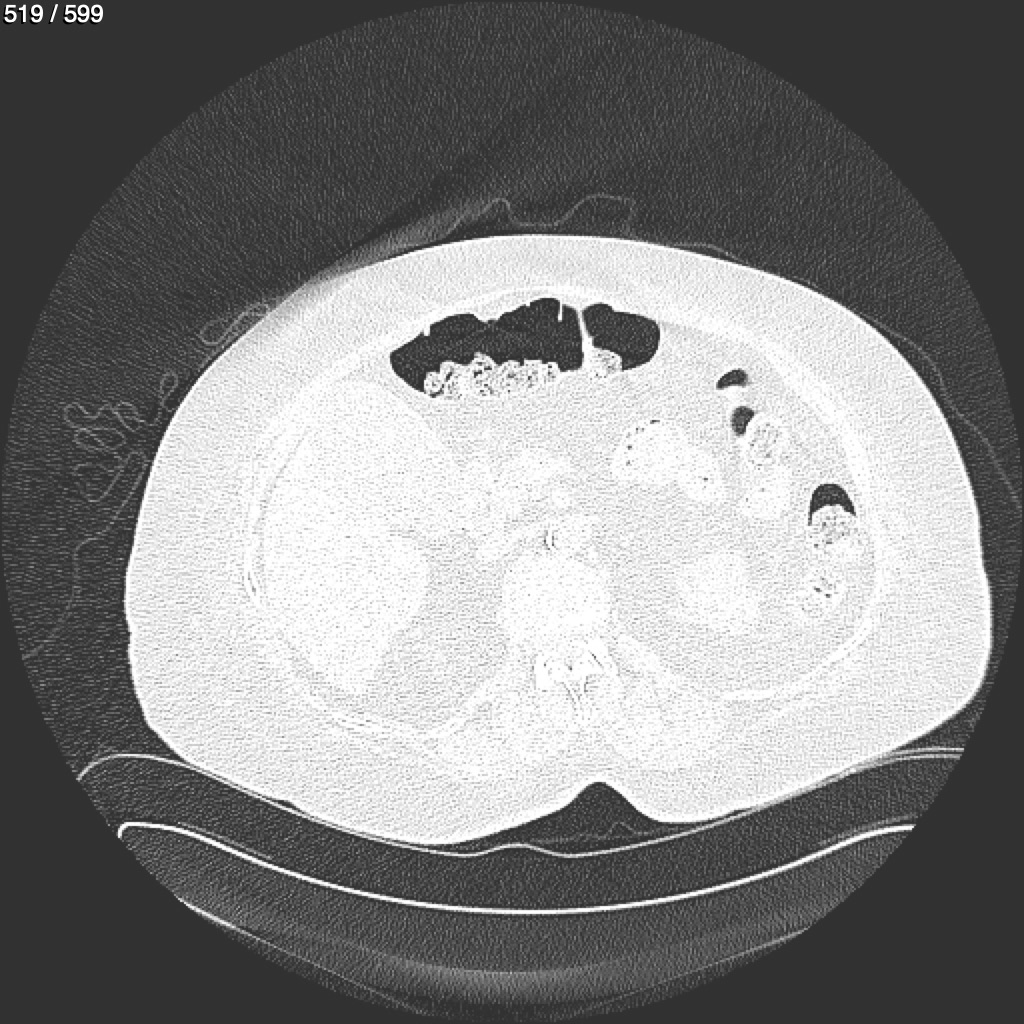

Home G​l​o​r​i​a​ ​G​l​a​d​y​s​ ​B​e​a​s​l​e​y​ ​-​ ​T​ó​r​a​x​ ​T​o​r​a​x​_​S​i​m​p​l​e​ ​(​A​d​u​l​t​o​)